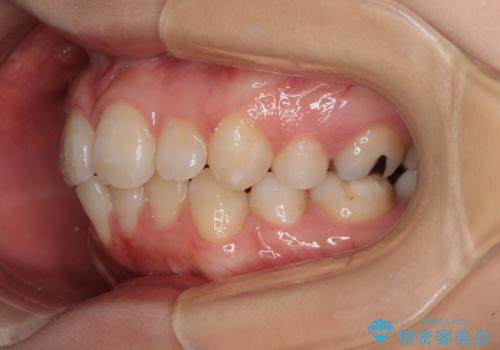

抜歯矯正の後戻り インビザライン・ライトによる矯正治療

- 矯正治療の後戻りを気にして来院された患者様です。

後戻りは軽微であったので、インビザライン・ライトにより矯正治療を行うこととしました。

治療途中、妊娠・出産があり、1年近く治療が停滞しましたが、無事に終了することができました。